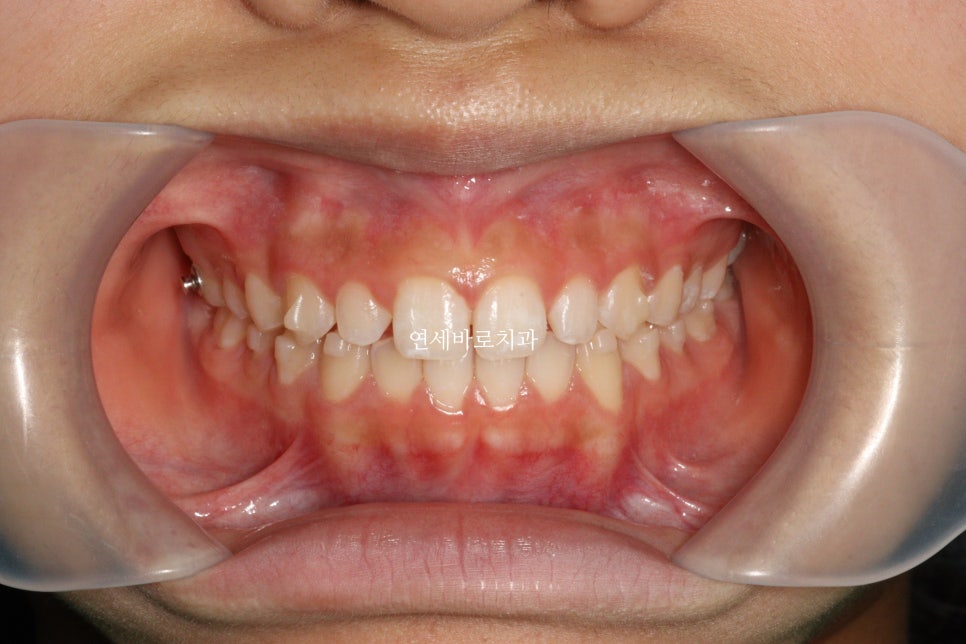

1월에 왔던 아이입니다. 어금니 교합은 너무나 좋아서 건들일것이 없었어요

앞니만 부분교정으로도 충분했습니다.

처음 치료를 시작한 날의 모습입니다.

아이가 하고 싶어한 만큼 당연히 열심히 잘 껴주었습니다.